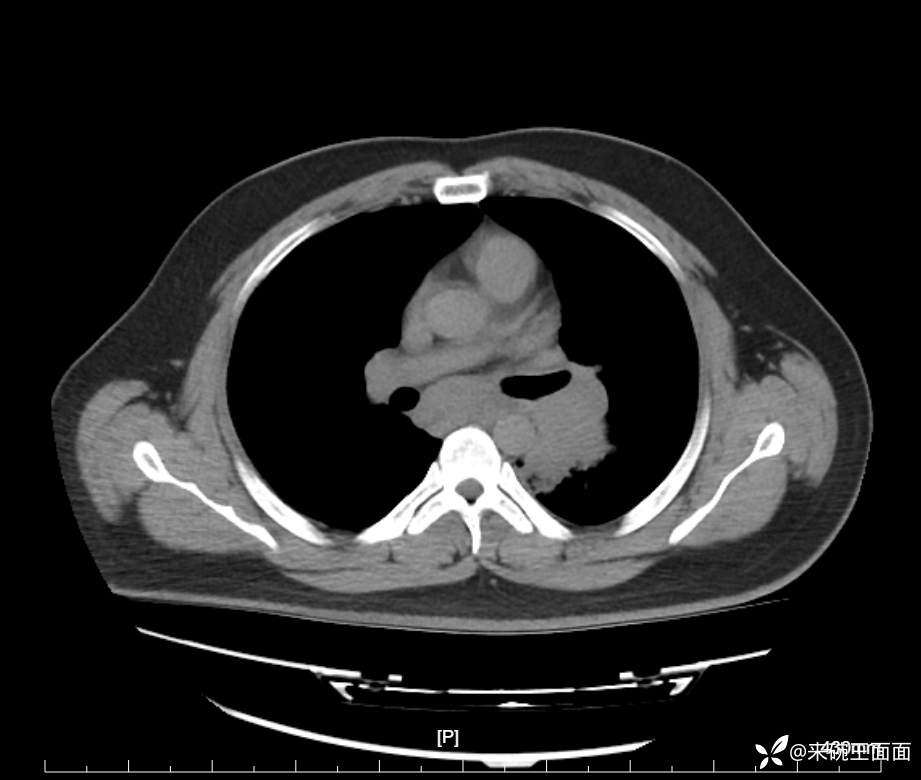

性别:男

年龄:27岁

主诉:胸闷胸痛数月余,休息后可自行缓解,无咯血症状。

个人史:数年吸烟史,具体不详。